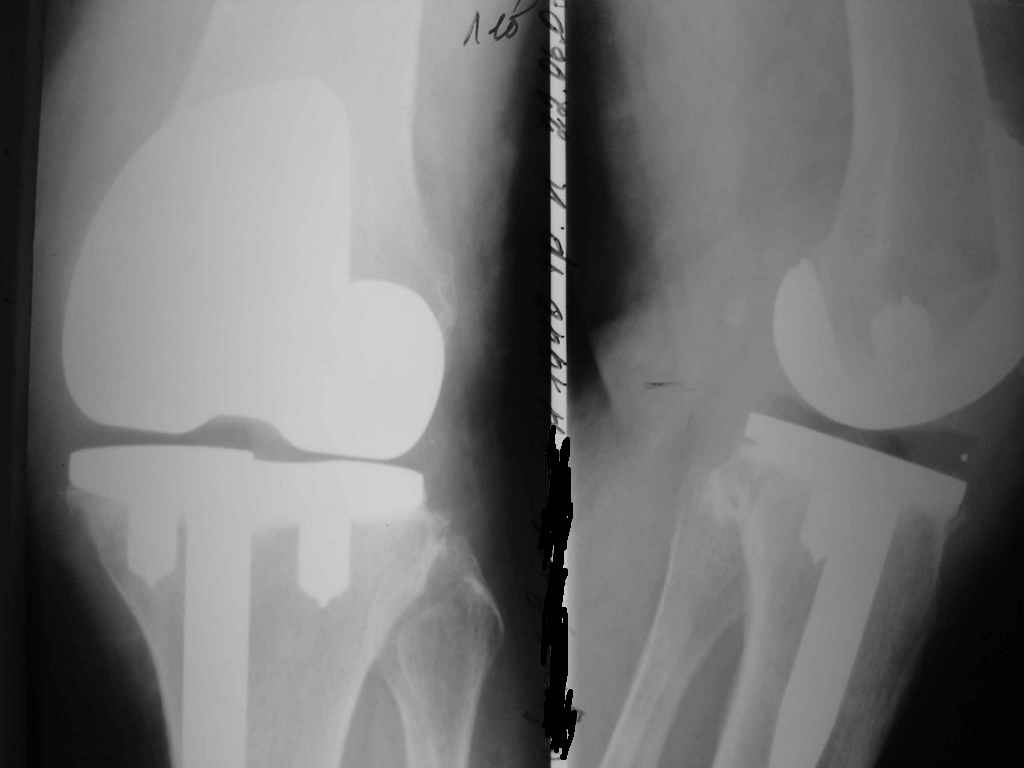

Уважаемые коллеги. Пациентка 65 лет соматически сохранна 6,5 месяцев назад выполнено замещениеколенного сустава интегральным эндопротезом Фримана Самуэльссона - цемент, по поводу ДОА. Послеоперационное течение с длительным субфебрилитетом. Местно без особенностей и выписана домой на 28 сутки с обьемом движений в колене 90 град. с частичной опорой. Дома отмечала субфебрильную лихорадку. Живет в небольшом поселке далеко от цивилизации. Контрольный осмотр в 3 месяца особых клинических проблем лечащий врач не нашел. Однако рентгенологически отмечены зоны остеопороза вокруг компонентов, на которые не обратил внимание. С 4 месяца отметила ухудшение - отек в колене, ограничение движений и боль. Лечилась у местного врача-хирурга (нестероиды и местно мазилки) - без эффекта. Обратилась только в 6,5 мес. Движения в суставе 20 град, отечность колена, выпот по УЗИ. Боль неопределенная, ходит с тростью. Лихорадки нет, в ан крови СОЭ 36 остальное норма, острофазовые тесты СРР повышен вдвое = 12 (при норме 6) Ревмотест - норма..Пункция - посев - роста не дает. Пробовали артроскопию - артрофиброз. Трудности осмотра из-законтрактуры и спаек. Рентгенограммы в динамике - в приложении (динамика с ухудшением). Вопросы:1. Инфекция? или остеопения местная? 2. Ревизия или подождать и полечить остеотропами? Благодарю заранее за любой совет. А Рыков. Хабаровск.

Показание к ревизии - нестабильность протеза (его компонентов) В приведённом Вами случае на Рг очевидная зона резорбции вокруг тибиального компонента следствие этого его нестабильность. Наиболее вероятна вялотекущая инфекция( судя по показателям крови и клиническим проявлениям: отек, боль, выпот и как следствие - ограничение функции)